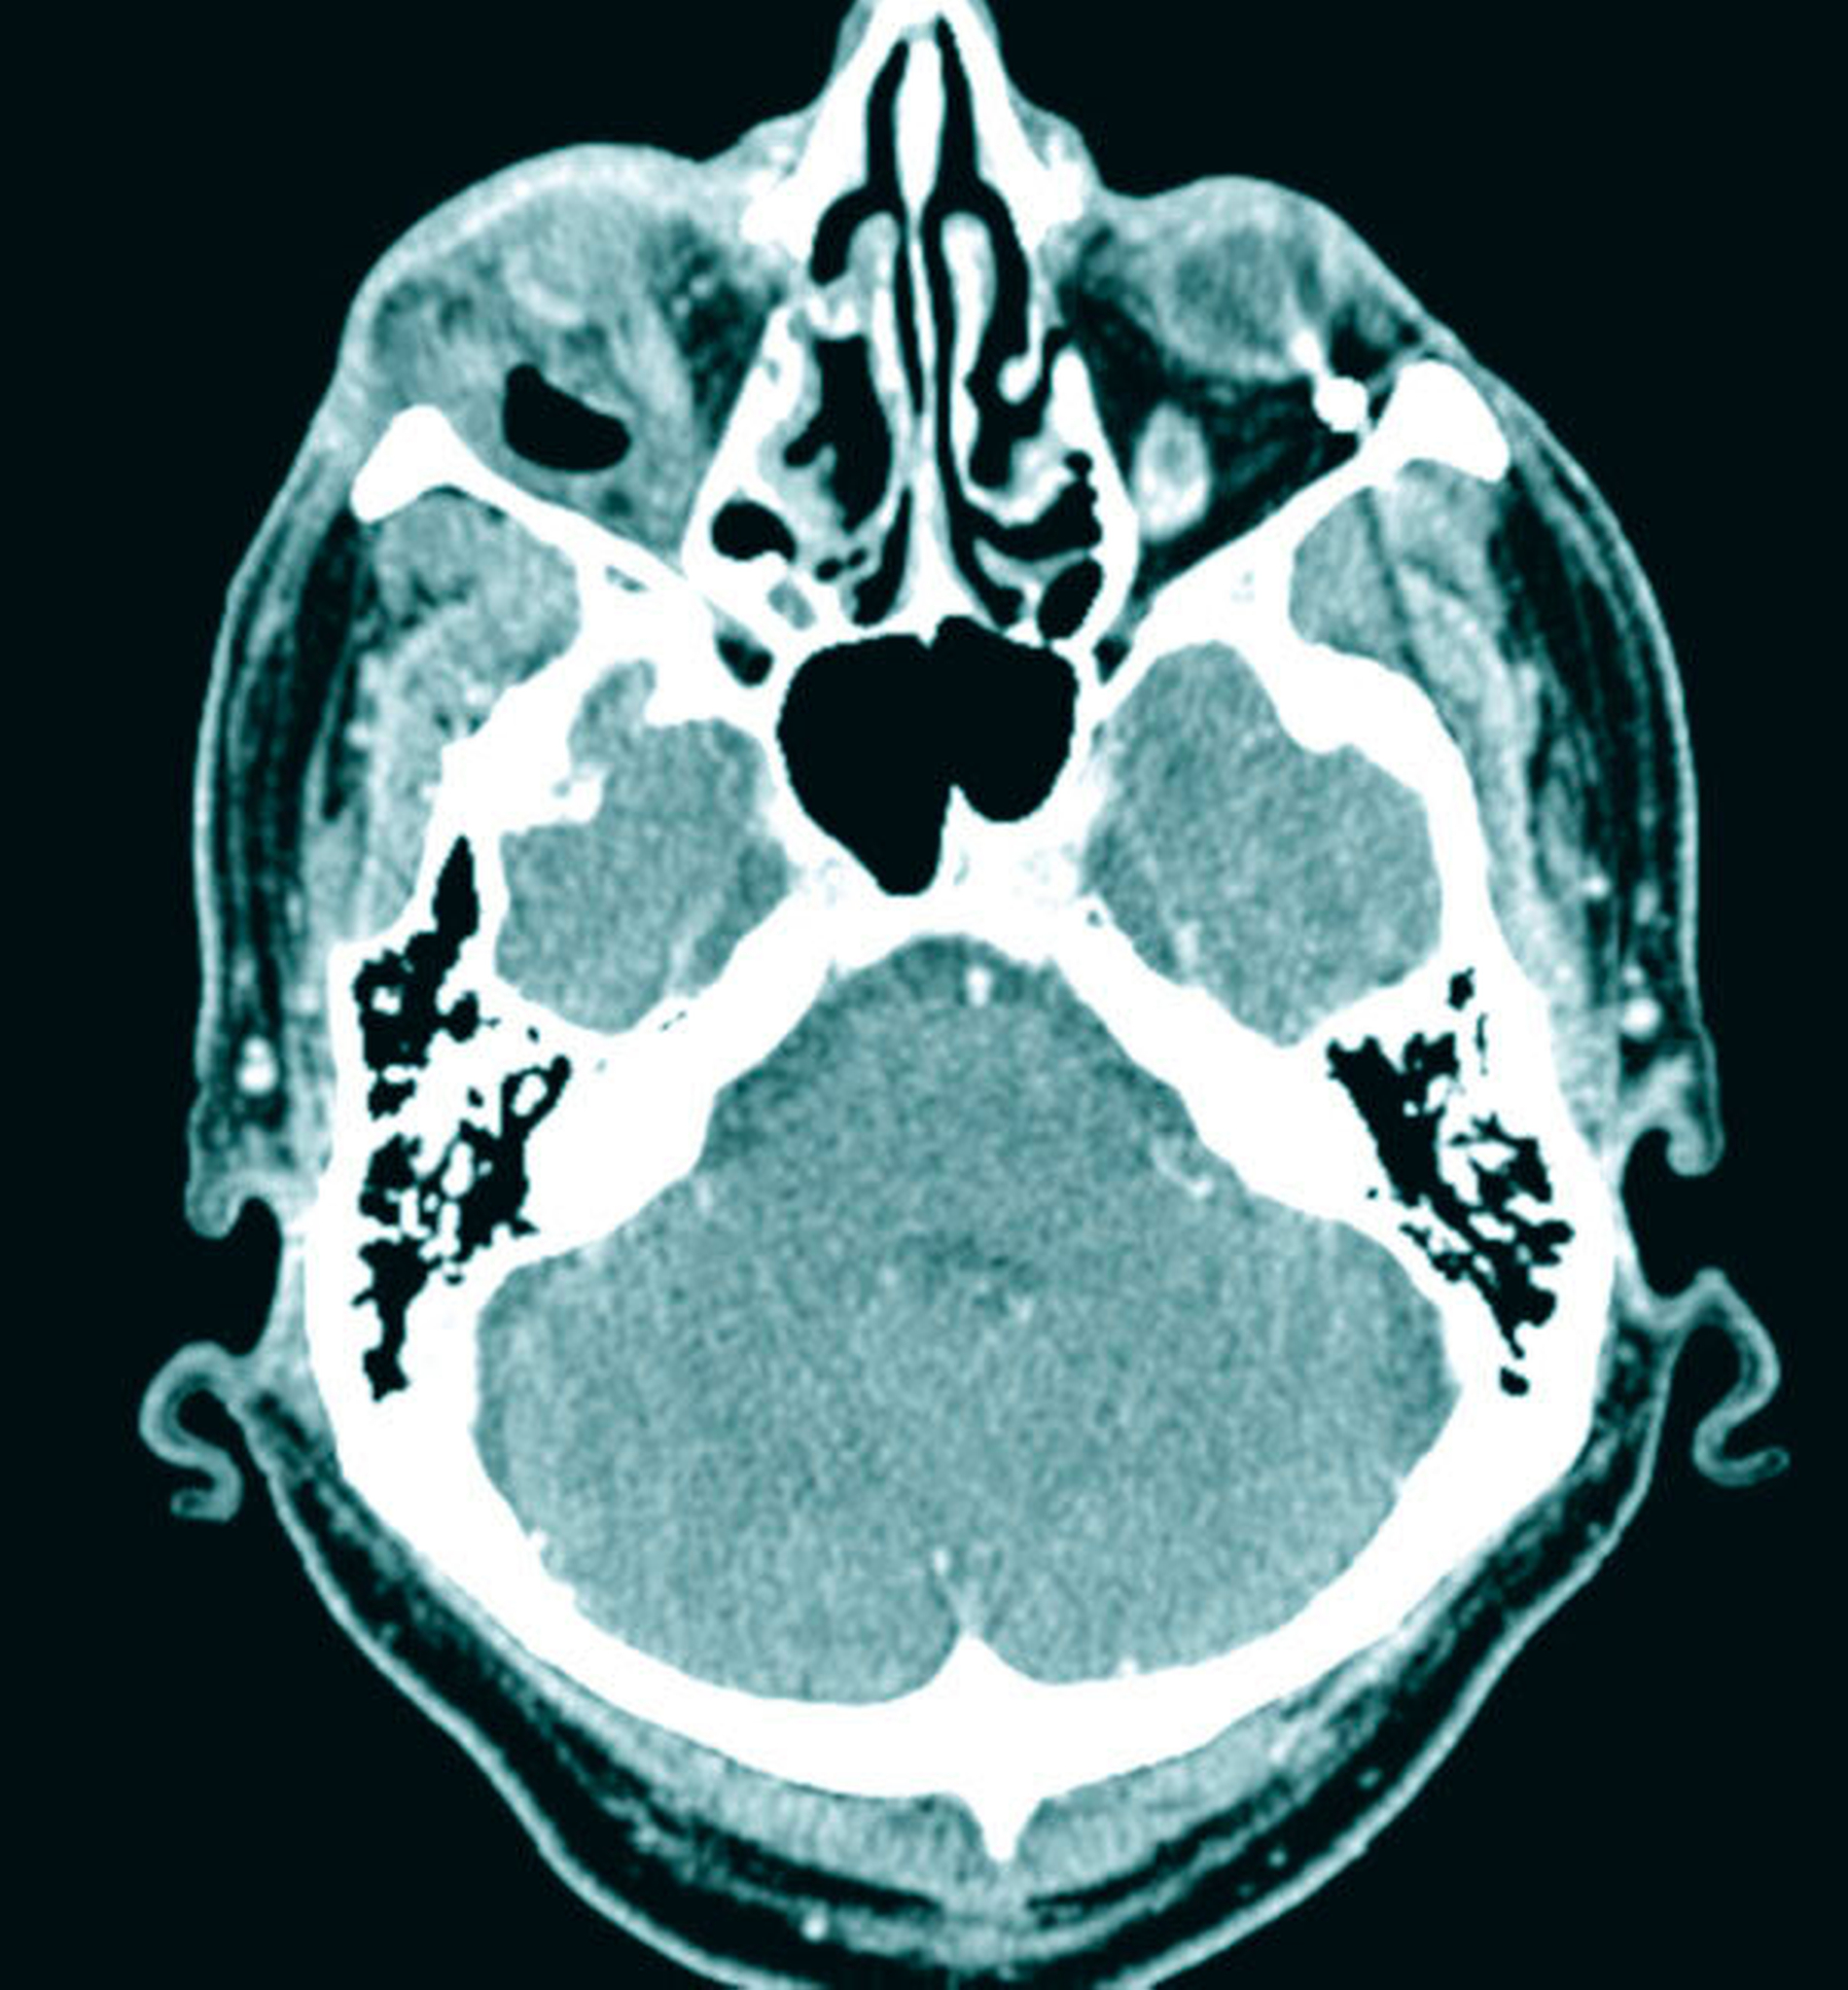

Wegen der unklaren Genese der akuten entzündlichen Veränderungen in der Orbital- und in der Periorbitalregion wurde eine CT- Diagnostik des Schädels mit Kontrastmittelgabe zum Ausschluss einer akuten retrobulbären Raumforderung veranlasst. Hierbei fand sich ein hochgradiger Verdacht auf eine Abszedierung in der rechten Orbita mit dem klinischen Bild von Protrusio bulbi und entzündlicher Mitreaktion der Augenmuskeln M. rectus lateralis und M. rectus inferior. Diese Veränderungen waren auch der Grund für die Weichteilschwellung am Unterlid. Ein intraorbitales Hämatom ließ sich ausschließen.

Zur weiteren Abklärung erfolgte nach zweidimensionaler Beurteilung die dreidimensionale Rekonstruktion der CT-Daten. Hierbei kamen die röntgenopaken Implantate im Kiefer sehr gut zur Darstellung und konnten in Bezug auf deren anatomische Lage beurteilt werden. Im atrophen Ober- und Unterkiefer zeigte sich ein mittelgradiger horizontaler Knochenabbau mit vertikalen Einbrüchen an allen Implantaten. In der rechten Maxilla regio 016 bestand nach Explantation eines rechtsseitigen Zygoma-Implantats ein circa 2 cm großer Defekt, der, aufgrund der verdrängten Weichgewebe und Lufteinschlüsse sicher bis in die mittlere, zentrale Orbita reichte.

Als auffälliger Nebenbefund fand sich auch auf der linken Seite ein 60-mm-Zygoma-Implantat, das 17 mm in die linke Augenhöhle ragte. Neu aufgetretene Veränderungen oder Behinderungen in diesem Bereich waren vom Patienten subjektiv nicht wahrgenommen worden, die Implantation selbst lag bereits zehn Jahre zurück.

Das Problem beim Einbringen der Zygoma-Implantate ist die korrekte Positionierung in den Jochbeinkörper. Hier kann es besonders beim liegenden Patienten leicht zu einer Via falsa kommen. Im vorliegenden Fall wurden die 60 mm langen Zygoma-Implantate statt in den Jochbeinkörper beidseits in die Orbita gesetzt. Das Problem der möglichen Fehlpositionierung langer Fixturen und von Zygoma-Implantaten wurde früh erkannt und es wurden hierfür Navigationshilfen entwickelt [Stella et al., 2000]. Schiroli et al. beschrieben 2011 eine Methode zur Computer-navigierten Insertion dieser Implantate. Sie wiesen auf der Basis ihrer Erfahrungen mit 25 Implantaten darauf hin, dass Komplikationen auch mit der Navigation nicht vollständig ausgeschlossen werden können [Schiroli et al., 2011].